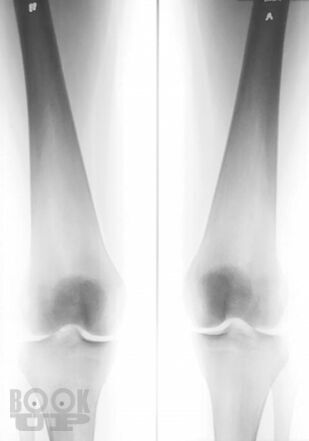

Болезнь Гоше относится к системным заболеваниям неопухолевой природы, в основе которых лежат наследственные дефекты метаболизма, приводящие к накоплению в органах и тканях нерасщепленных продуктов нормального обмена веществ. В случае болезни Гоше дефектом метаболизма является дефицит фермента, ответственного за метаболизм липидов.